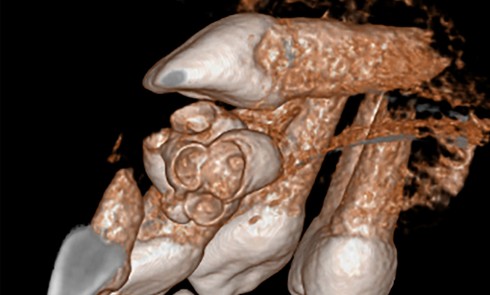

Article réservé à nos abonnés Extraction, implantation et temporisation immédiate : recycler la dent naturelle ? À propos d’un cas clinique

Les protocoles d’extraction-implantation immédiate, décrits pour la première fois en 1976 par Schulte et Heimke [1], se sont progressivement développés...